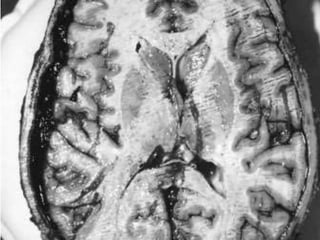

mli1. Evidence of application of blunt force. Accidental Homicidal Suicidal – Unusual ARTIFICIAL BRUISES 2. Though in itself a trivial injury, Lies in the site & the organs involved. Contusion of vital organs heart and brain.Caused marked derangement of functions & even death

3. Volume of blood- Circulating Diminished – Due to Extravasation4. Patterned Bruising Nature of agent used.5. Healing – Determination of age.6. Bruising- Scalp- It is better. 7. Bruising over the particular part of the body-Indicate some peculiar offence Ex : On the Neck Inner Side of Thigh – FemalesIndicate Sexual Assault    small bruises The so called “six Penny Bruises”8.Character & manner of injury may be known from its distribution.

complications1. Contusion contain 20- 30 ml of blood or even more. Multiple contusion can cause death from shock & internal haemorrhages.2. Gangrene & death of tissue.3.Good site for Bacterial growth.

Late causes: Disseminated Intravascular Coagulation:Follows whole range of traumatic, infective and other acute events. Abnormal activation of coagulation process.Brain and placenta are particularly potent. Causes of death due to injury:

mli1. Evidence ofapplication of blunt force. Accidental Homicidal Suicidal – Unusual ARTIFICIAL BRUISES 2. Though in itself a trivial injury, Lies in the site & the organs involved. Contusion of vital organs heart and brain.Caused marked derangement of functions & even death

3. Volume ofblood- Circulating Diminished – Due to Extravasation4. Patterned Bruising Nature of agent used.5. Healing – Determination of age.6. Bruising- Scalp- It is better. 7. Bruising over the particular part of the body-Indicate some peculiar offence Ex : On the Neck Inner Side of Thigh – FemalesIndicate Sexual Assault small bruises The so called “six Penny Bruises”8.Character & manner of injury may be known from its distribution.

complications1. Contusion contain20- 30 ml of blood or even more. Multiple contusion can cause death from shock & internal haemorrhages.2. Gangrene & death of tissue.3.Good site for Bacterial growth.

Late causes: DisseminatedIntravascular Coagulation:Follows whole range of traumatic, infective and other acute events. Abnormal activation of coagulation process.Brain and placenta are particularly potent. Causes of death due to injury: